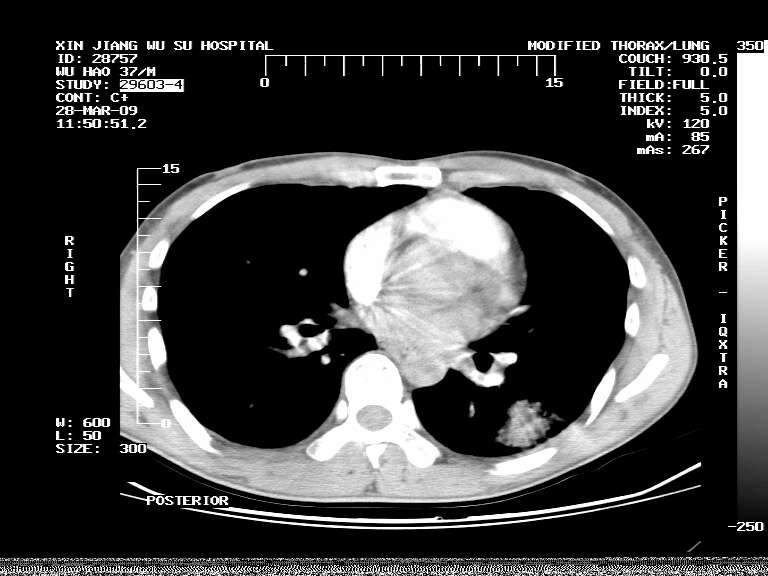

男,37岁,体检胸透发现阴影。

患者体检发现 无症状 左肺下叶占位,边缘模糊,可见血管聚束、分叶、胸膜牵拉,增强呈不均匀性强化。 首先考虑左肺下叶周围型肺癌,建议穿刺活检。

患者体检发现 无症状 左肺下叶占位,边缘模糊,可见血管聚束、分叶、胸膜牵拉,增强呈不均匀性强化。 首先考虑左肺下叶周围型肺癌,建议穿刺活检。支持!

左肺下叶见一结节病变,边缘欠清不光滑,与胸膜粘连且胸膜局限性增厚,注药后呈环形强化,动脉期壁呈明显点环状强化,静脉期壁强化减低,中心密度低无强化,灶周无明显的卫星灶和水肿区(晕征)---考虑周围性肺癌,不除外感染性病变,建议穿刺活检。

病灶强化太明显,病人较年轻。考虑炎性假瘤与周围型肺癌鉴别,以前者可能性,建议抗炎治疗后复查。

左肺下叶软组织病灶,密度较高,内见点状钙化,其周围见子灶,邻近胸膜扁平样增厚.c+病灶强化明显,中心强化弱.诊断:左肺下叶结核瘤.